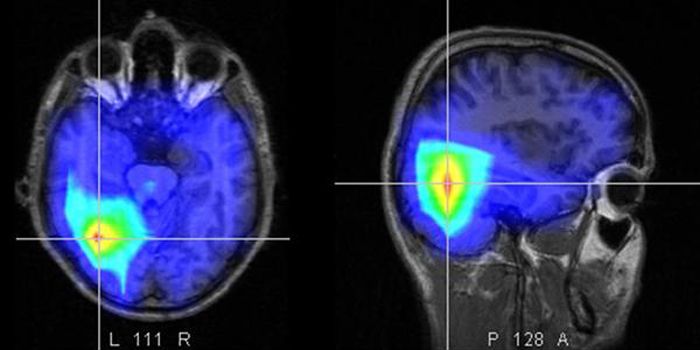

El ACV se produce cuando el flujo se sangre es obstruido; y existen dos tipos de ataque, el isquémico y el hemorrágico.

El 75 por ciento de los accidentes se producen por eventos de tipo isquémico y se dan ante la formación de coágulos de sangre en las arterias que nutren al cerebro o cuando un coágulo que se generó en otra parte del cuerpo se instala en el cerebro. Los de tipo hemorrágico provocan sangrados en el interior del cerebro o las capas que lo rodean ante la rotura de un vaso sanguíneo.